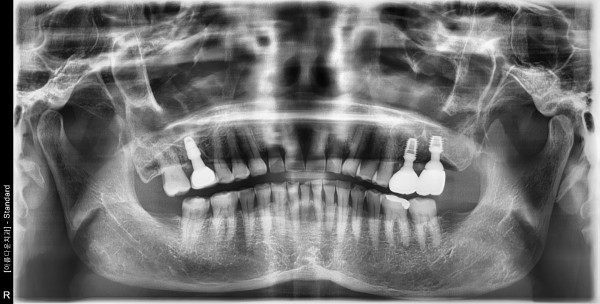

65세여자 좌측상악 상악동거상술및임플린트식립